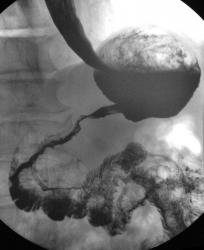

Желудок

Осмелюсь предположить что в антральном отделе желудка есть рак,  инфильтративная форма.

На серии представленных вами снимков сделанных во время скопии, отмечается регидность участка и утолщение слизистой(отмечено стрелками), жалко только  что не была выведена петля 12п.к. в положении стоя, там бы мы увидели четко антральный отдел:

Да это один и тот же больной.Гистологическая верификация-аденокарцинома.И в кишке и в пищеводе дивертикулы.

В антарльном отделе  не толко ригидность ,а стойкое циркулярное сужение.А вот по большой кривизне можно сказать ,что ригидность, хотя контур стенки ровный четкий, но при двойном контрастировании толком не расправился, да и перистальтика почти отсутствует

Случай интересный, в плане сочетания дивертикула пищевода и тонкого кишечника с органикой желудка.